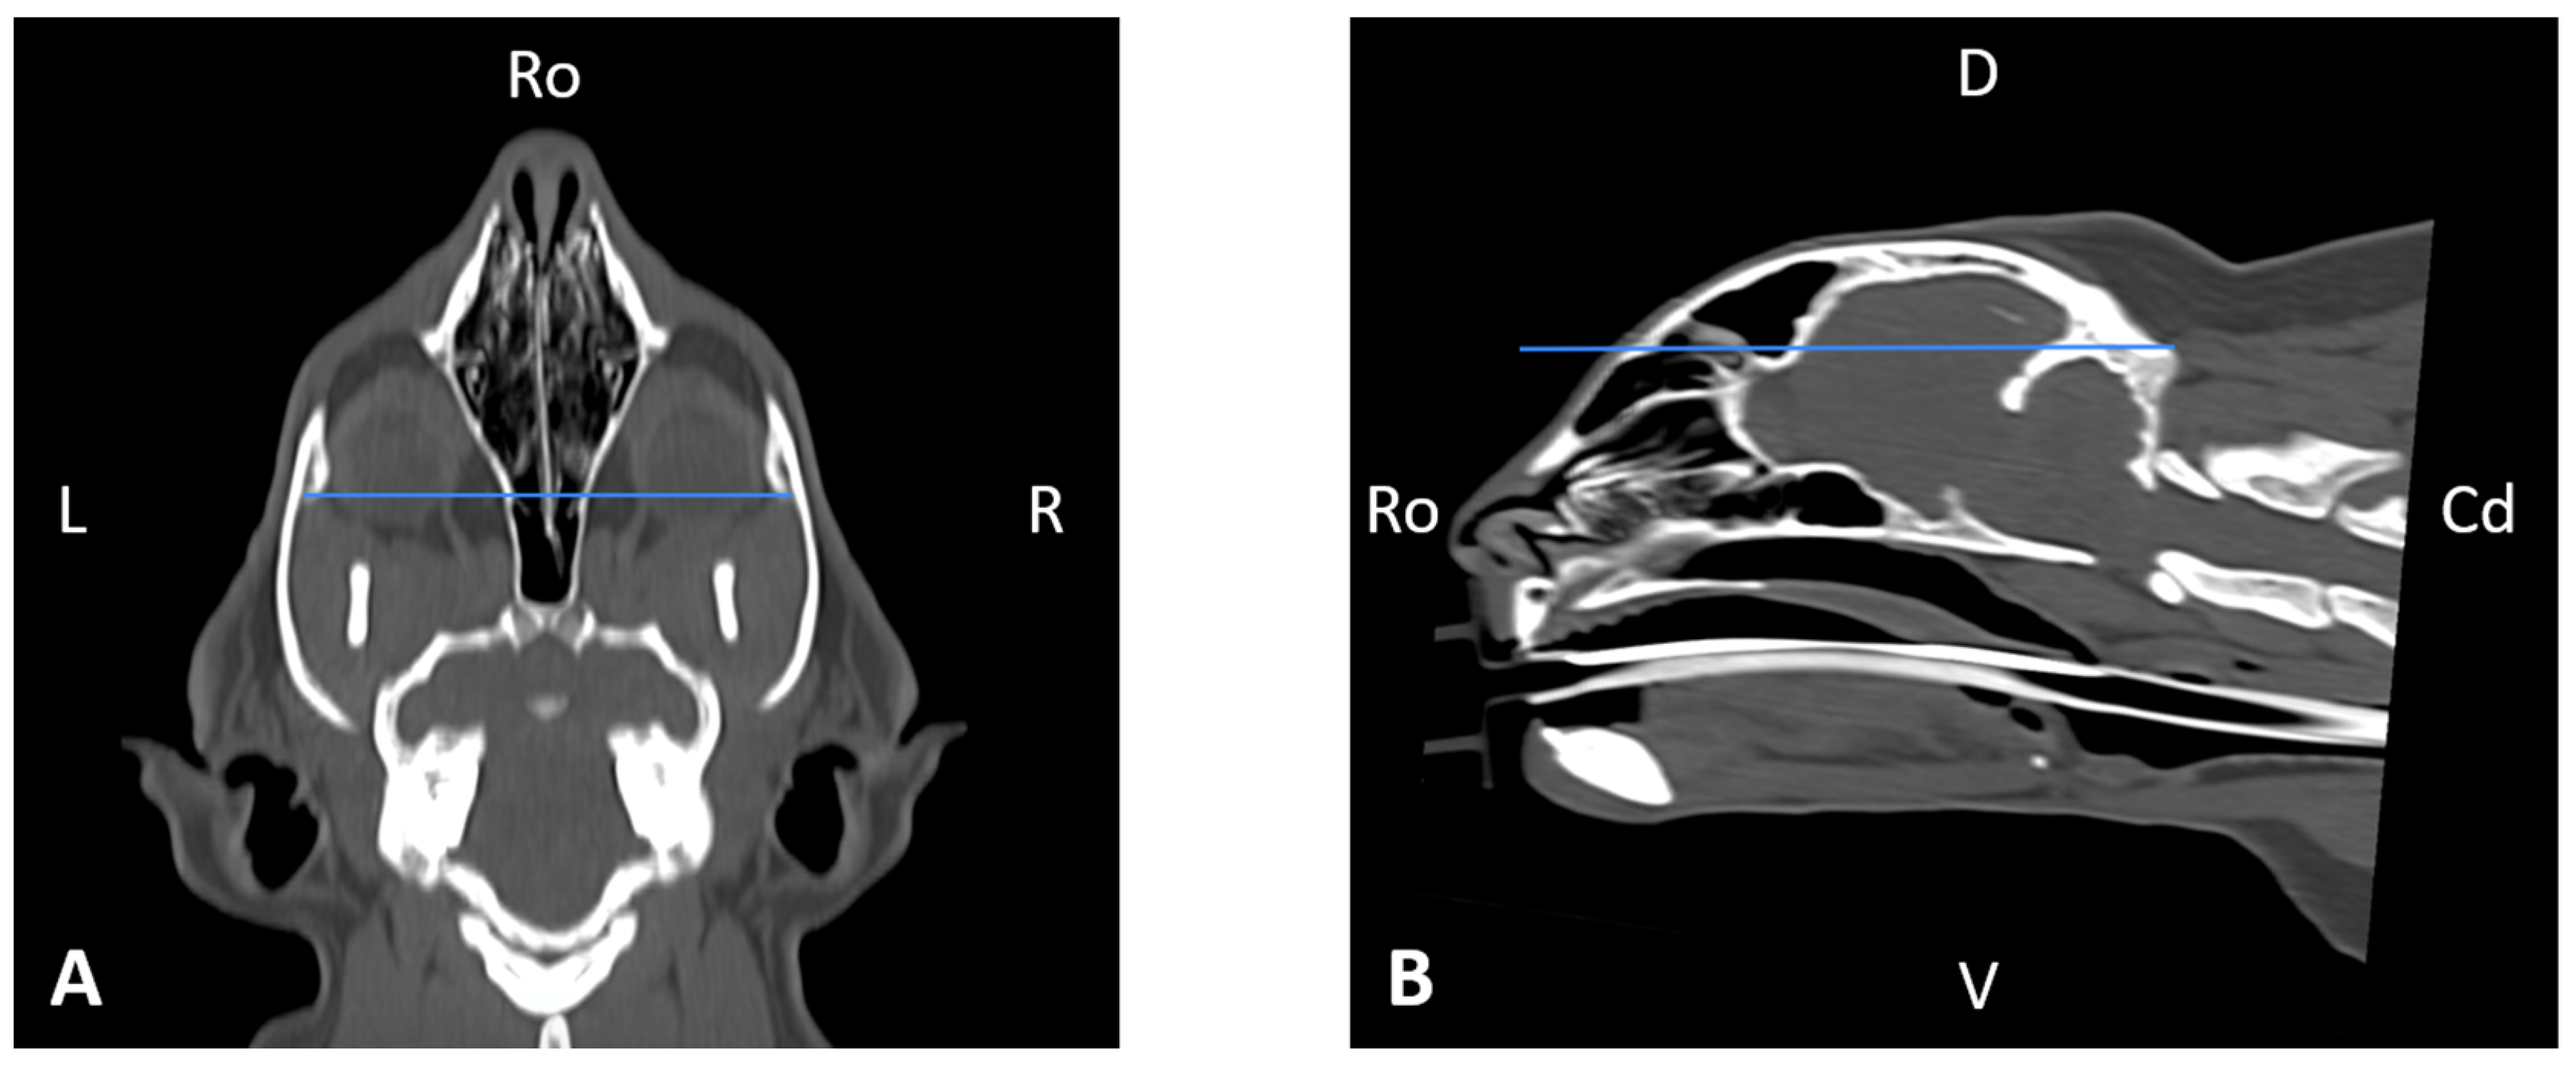

In order to perform the linear measurements described in Table 1, firstly, rotational misalignment of the head was corrected by aligning the images in the three planes, as demonstrated in Figure 1. The sagittal plane (Figure 1A) was aligned at the level of the nasal septum and the interincisive midline; the transverse plane (Figure 1B) was oriented perpendicular to the hard palate; and the dorsal plane (Figure 1C) was parallel to the hard palate. Since the computer program used allowed for the simultaneous visualization of the three anatomical planes (sagittal, transverse, and dorsal), the identification of the measurement planes and the delimitation of the anatomical structures to be measured was performed with greater precision.

Figure 9. Skull width (SW) measured on a dorsal CT image (A) (blue line), and skull length (SL) measured on a sagittal CT image (B) (blue line). Cd, caudal, D, dorsal, L, left, R, right, Ro, rostral, V, ventral.